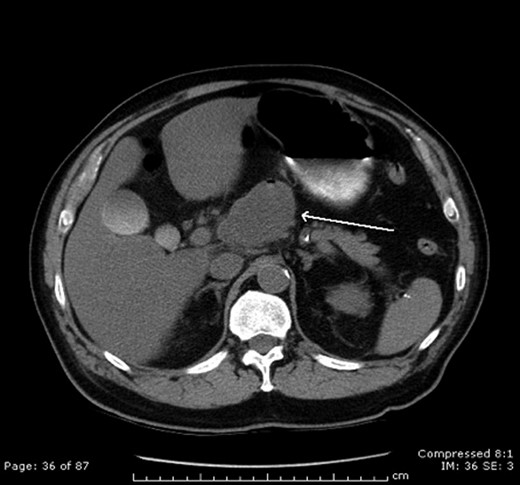

Before the follow-up CT, the patient presented to the emergency department with intractable abdominal pain. Initial vital signs and laboratory findings were normal. His physical examination showed significant epigastric tenderness. An abdominal CT showed that the pancreatic mass had doubled in size. There also appeared to be air present in the mass making a pseudocyst or abscess more likely (Fig. 1). Gastroenterology performed a repeat EUS that was again non-diagnostic.

CT scan demonstrating LEC. Note the air present in the cystic mass.